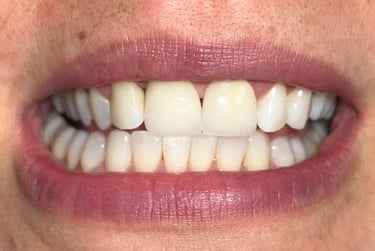

Coroas em Dissilicato de Lítio

Todos os caso a seguir estão associadas a clareamento dentário

Antes

Depois